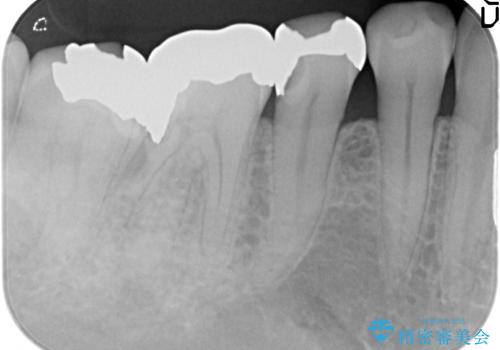

- 右下5番目の歯がしみるので診て欲しいといらっしゃった方の症例です。

古い銀歯及び虫歯を除去後、PGA(ゴールド)インレーによる修復を行いました。